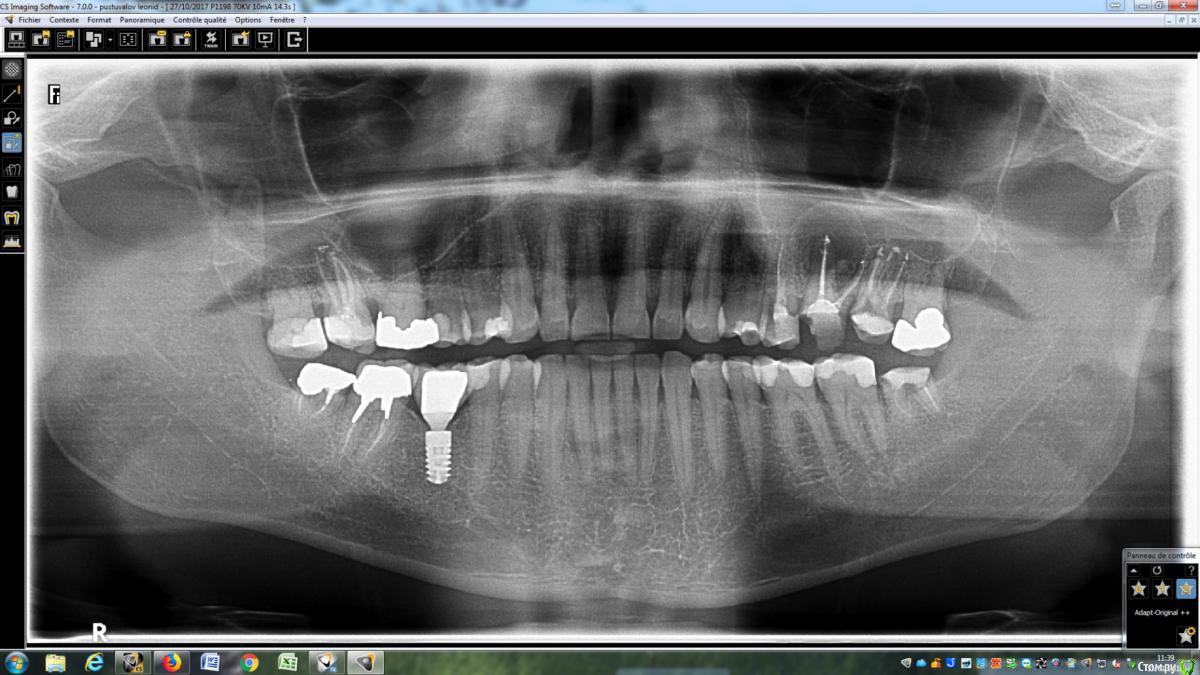

LeoRuss Опубликовано 20 февраля, 2018 Поделиться Опубликовано 20 февраля, 2018 (изменено) Здравствуйте уважаемые метры, в очередной раз обращаюсь к вам за советом.Чуть меньше года назад эндодонтическим методом в полном соответствии с вашими рекомендациями была пролечена киста 26.( http://forum.stom.ru/topic/34508-podsadka-kosti-pri-kiste-nuzhna-li-v-dannom-slucha/ ) При вскрытии зуба выявилась неприятная картина: оба титановых штифта в далеком ‘94м были завернуты мимо корневых каналов прямо в челюсть ;(Док все демонтировал, прочистил под микроскопом и каналы и дыры от штифтов и замуровал МТА : спустя 8 месяцев - 10/2017 : И вроде бы все чудесно, но пару раз за это время десна вокруг зуба воспалялась, и зуб становился более подвижным, но все проходило после 2-3-5 дневного интенсивного полоскания хлоргексидином. Три недели назад была наконец то установлена коронка на соседний 27й, десна с внутренней стороны 26ки тогда была тоже припухшей и протезист посоветовал сходить на контроль к эндодонтисту. Напросился и сходил через неделю, десна за это время еще чуть распухла (только со стороны языка), стало больно при легком нажатии на десну в районе верхушки корня ближнего к 25ке и при покачивании зуба. Док сделал снимок, сказал что все чисто и он понятия не имеет почему все надулось. Вариант удаления забраковал, сказал что по его мнению все хорошо, и можно уже ставить коронку. А вот в импланте смысла никакого, тем более что кости для него пока недостаточно, тк межкорневая область еще не дозаросла. Посоветовал терпеть и.. поставить коронку, тк нагрузка на зуб при жевании должна активировать заживление.Но жевать на этой стороне я стал почти месяц назад, сразу после установки временной коронки на 27, вот с тех пор с 26кой все хуже и хуже. За последние полнедели опухоль сильно увеличилась, и между 25/26, и в сторону нёба, дергает в ритме пульса. Появились отголоски боли в носоглотке и в заглазье.Терпеть уже плохо получается, да и смысла не вижу. Вижу два варианта:1. Удалять 26 чтоб не мучаться, с последующей имплантацией, но как быть с нехваткой кости?2. Вскрыть каналы и прочистить еще раз, но даст ли это хоть что то, да и возможно ли в принципе? В любом случае хотел бы узнать ваше мнение, спасибо ! Изменено 20 февраля, 2018 пользователем LeoRuss Ссылка на комментарий

LeoRuss Опубликовано 20 февраля, 2018 Автор Поделиться Опубликовано 20 февраля, 2018 Как вы и говорили сделали томограмму и все прояснилось: киста зажила наполовину но.. по вертикали, та часть кисты что со стороны щеки затянулась, а вот со стороны языка, только чуть. Видимо повлияла перфорация челюсти штифтом, или МТА туда просто не попало. Увы, теперь уже только удаление. Еще раз огромное спасибо ! Ссылка на комментарий